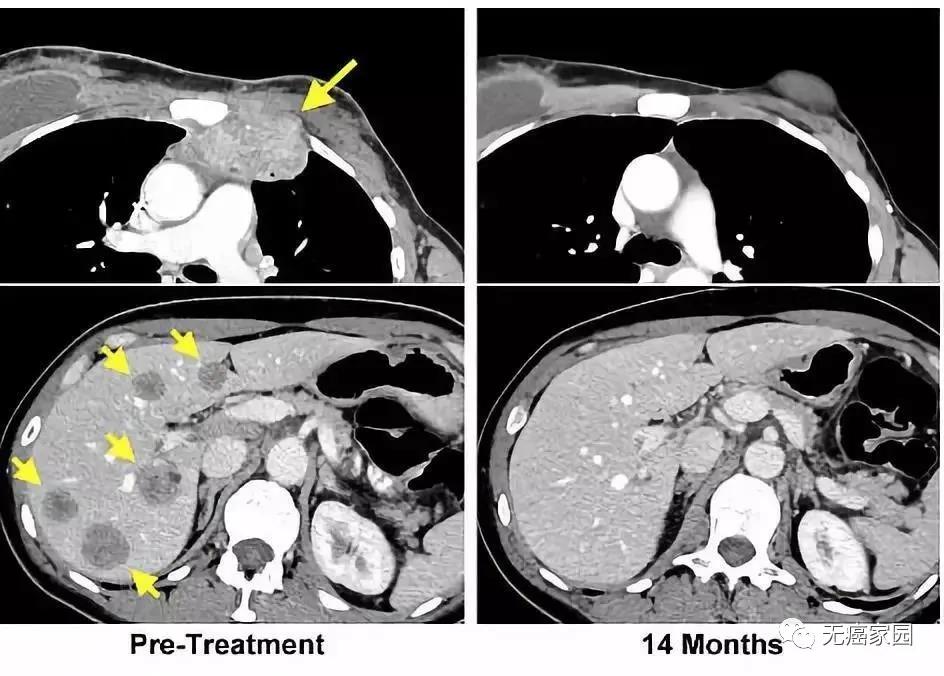

左图黄色箭头是治疗前肿瘤位置;右图是治疗结束14个月后的复查:肿瘤完全消失

一周过后,Judy Perkins感觉自己的身体起了明显的变化。比如她长在胸部的肿瘤,感觉逐渐缩小。又过了一两周,胸腔内的肿瘤荡然无存。